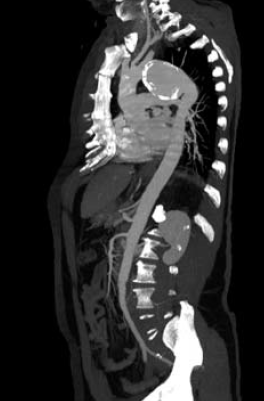

1. ábra.

Autóbalesetben sérült 26 éves ffi. DSA felvétele 3 héttel a baleset után. Az isthmicus szakaszon álaneurysma ábrázolódott.

1. 26 éves ffi autóbalesetben utasként szenvedett el mellkasi zúzódást, bordarepedést és tüdő contusiót. A kiszélesedett mediastinum és kis mennyiségű mellkasi folyadékgyülem vetette fel isthmicus tompa aortasérülés lehetőségét, amit DSA vizsgálattal igazoltunk. Hypotenziv kezelés mellett keringése stabil, a mediastinum kiszélesedése és haematologiai statusa nem változott. 3 héttel a sérülést követően bal oldali thoracotomia útján aorto-aorticus Dacron grafttal, mesterséges keringés alkalmazása nélkül, interpositiot végeztünk (1.,2.,3. ábra).